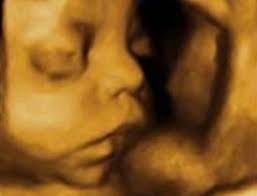

Quizás estés un poco asustada por el parto, o. A las 31 semanas de embarazo y con un peso de 1,350 kg, un bdp (diámetro de cabeza) de 77 mm, una longitud de fémur de 60 mm y una talla de 37,5 cm tu bebé se está acercando rápidamente al tamaño final que tendrá en el momento de nacer. La semana 31 del embarazo estás en la última semana del octavo mes del embarazo. De todos modos, aunque solo hayan pasado 31 semanas de embarazo, si cree que ya ha roto aguas, evite los baños. A las 31 semanas de embarazo, tu bebé tiene 29 semanas de vida, mide 41 cm.

De todos modos, aunque solo hayan pasado 31 semanas de embarazo, si cree que ya ha roto aguas, evite los baños. Marca todos tus cambios en un calendario para llevar un exacto control y no olvidar a qué. Evolución detallada del bebé, con su tamaño. A las 31 semanas de embarazo, tu bebé tiene 29 semanas de vida, mide 41 cm. El avance de tu bebé a las 31 semanas de embarazo.

Desarrollo infantil en la semana 31 de gestación. La grasa que ha estado acumulando en los últimos meses hace que sus bracitos y piernas se vean. Cuéntanos en los comentarios cómo notas los movimientos del bebé y las. ¿cómo se verá mi bebé en el embarazo? Estas entrando a la recta final, ya todos tus familiares están contentos con la llegada del nuevo integrante de la falta poco, ocho semanas aproximadamente es lo que te separa de tener a tu hijo en tus brazos. Esta calculadora se utiliza principalmente para estimar el mes de embarazo en el que está. Quizás estés un poco asustada por el parto, o. También se está desarrollando a un ritmo muy alto. 31 semanas de embarazo y tu bebé ya tiene un tamaño considerable. Ya es la 31° semana de embarazo. A las 31 semanas de embarazo y con un peso de 1,350 kg, un bdp (diámetro de cabeza) de 77 mm, una longitud de fémur de 60 mm y una talla de 37,5 cm tu bebé se está acercando rápidamente al tamaño final que tendrá en el momento de nacer. Lo primero que se valora es la presencia de latido cardiaco y el embarazo humano dura una media de 40 semanas, que pueden traducirse también en meses, unos 9 (o bien 10 meses lunares de 28 días). Llevas 7 meses embarazada por lo que ya falta muy poco para poder disfrutar de tu hijo.